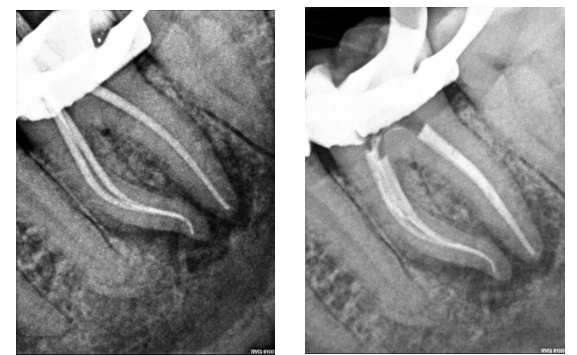

Figure 2a: Master cone radiograph. The apical foramen exits the root laterally on the mesial root. An apex locator is essential in these cases to determine the WL. b) Mid-fill radiograph - The distance between with apical constriction and root terminus increases with age due to secondary cementum deposition at the root apex (Figure 1)

- Two dimensional: radiographs are two-dimensional images and offer a limited perspective particularly in the bucco-lingual plane (Figure 4)

Figures 4: Radiographs are two-dimensional images offering a limited perspective in the bucco-lingual plane. This makes WL determination challenging in some cases. Root canal treatment LL6 Figure 4a) Preoperative radiograph. Figure 4b: Master cone radiograph. The four separate canals are terminating at different lengths. It would not have been possible to estimate this accurately using a preoperative radiograph, and an apex locator was essential. Figure 4c: Postoperative radiograph